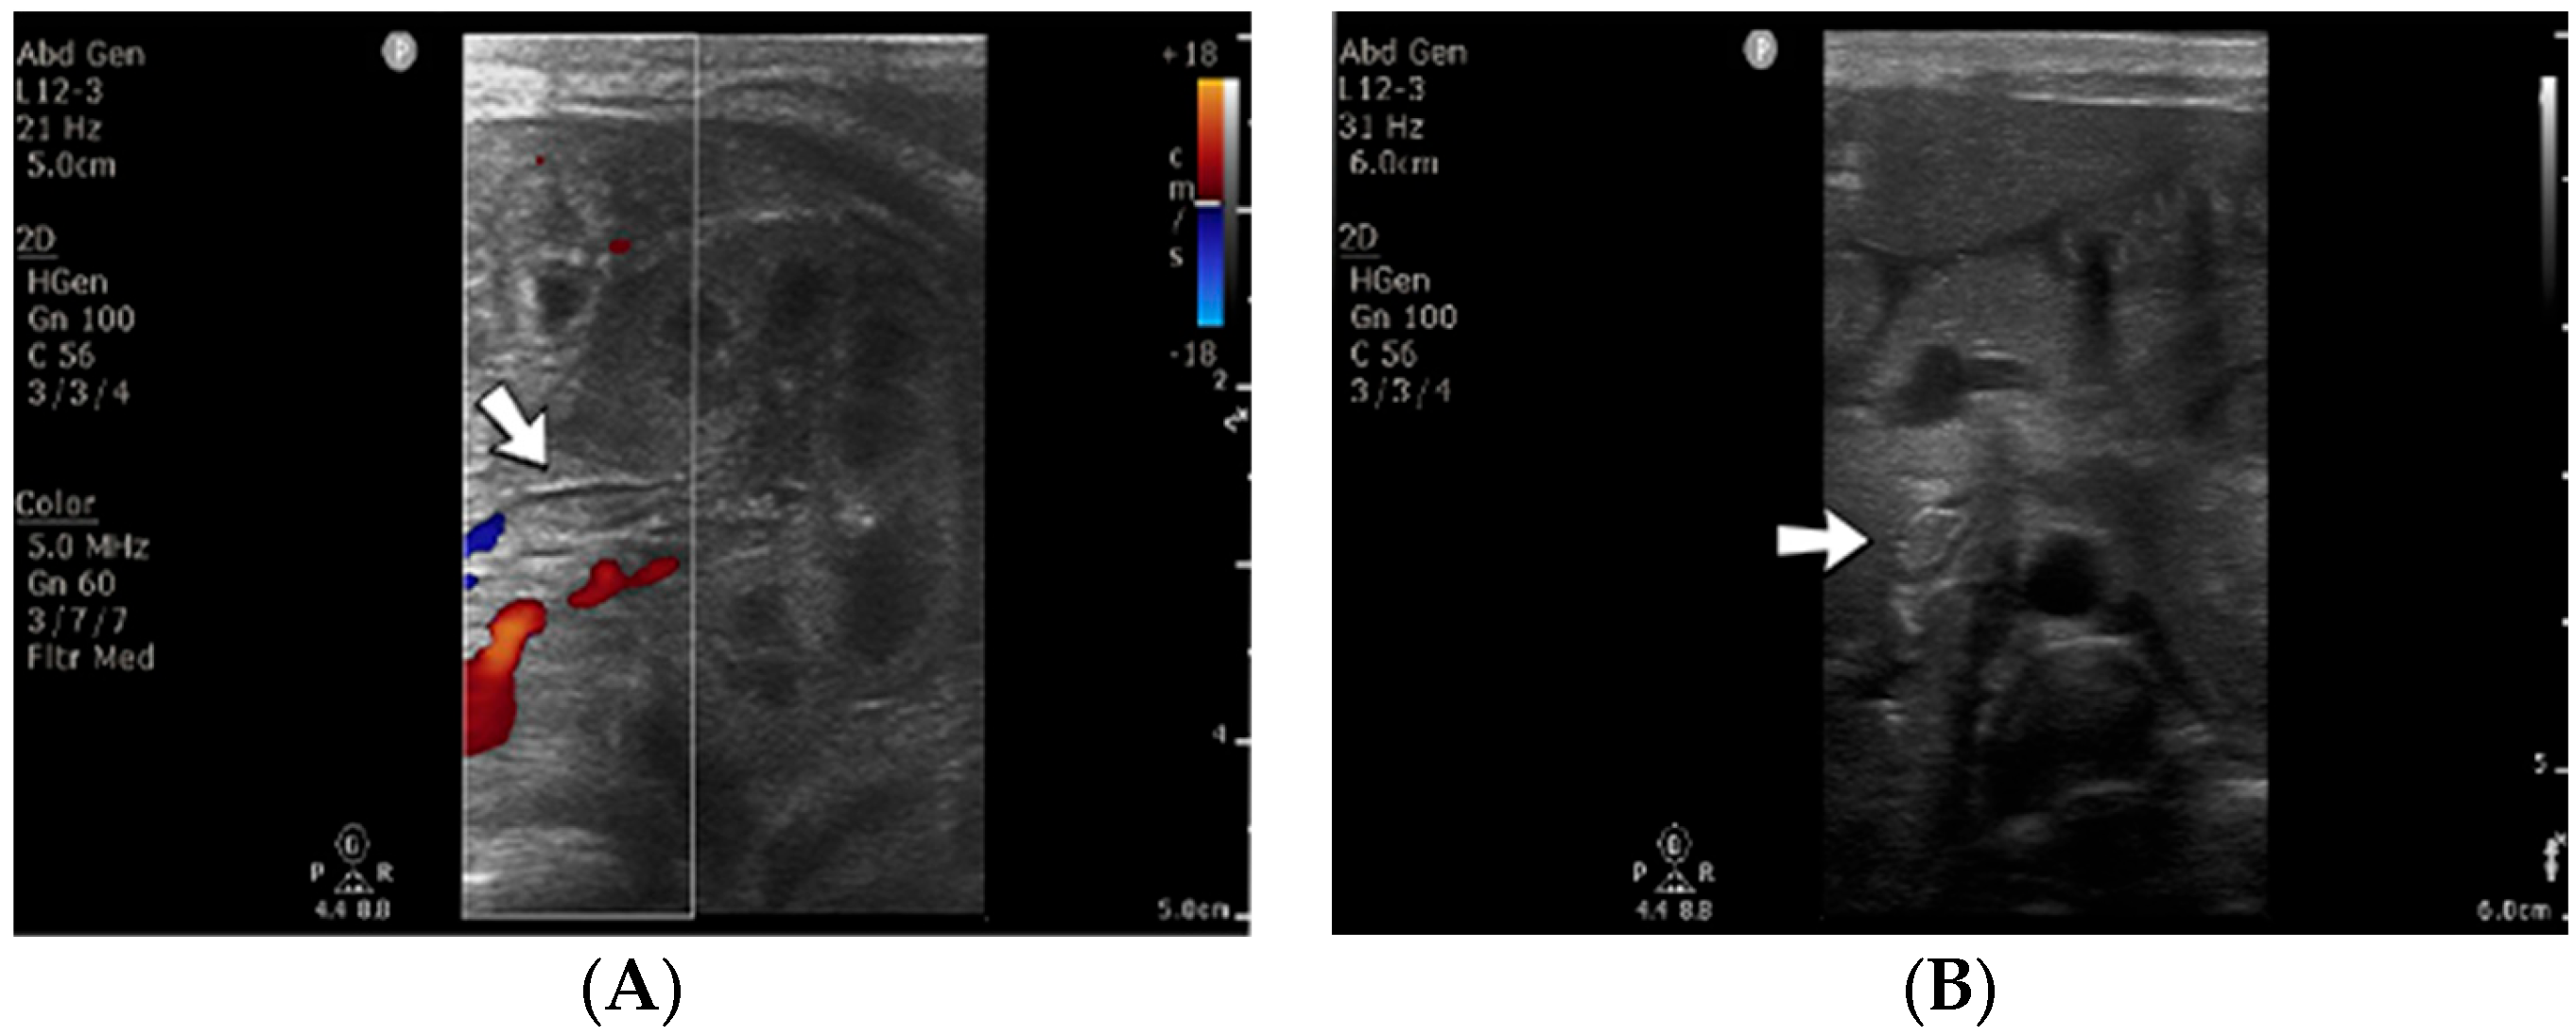

4.34. Case No. 34—Postnatal Thrombosis of the Right Axillary Artery

A 10-day-old female neonate (36 weeks, 2.37 kg), known before birth with Dandy–Walker Syndrome, presented with hydrocephalus and severe coarctation of the aorta. Two central arterial lines were placed—in the right brachial and the left femoral arteries—and the aortic defect was corrected. One day later, hematoma of the right arm and ecchymosis near the insertion site of the brachial arterial catheter were noticed. Vascular ultrasound could not reveal any blood flow on the axillary or the proximal brachial arteries, leading to the removal of the central arterial catheter (Figure 14). Continuous heparin infusion was initiated, followed by treatment with enoxaparin. Later, blood flow was reestablished on both axillary and brachial arteries.

Figure 14.

No blood flow on the axillary or the proximal brachial arteries on vascular ultrasound.

Genetic testing confirmed inherited thrombophilia, with a positive MTHFR C677T homozygous gene mutation and Antithrombin, Protein S, and Protein C deficiencies. Normal PAI-1 levels were detected. There was a positive family history of maternal thrombophilia (MTHFR A1298C, MTHFR C677T, PAI-1 4G/5G promoter, and Factor XIII (Val34Leu) heterozygous gene mutations and Protein S deficiency), treated with enoxaparin and acetylsalicylic acid during pregnancy. There were no maternal miscarriages.